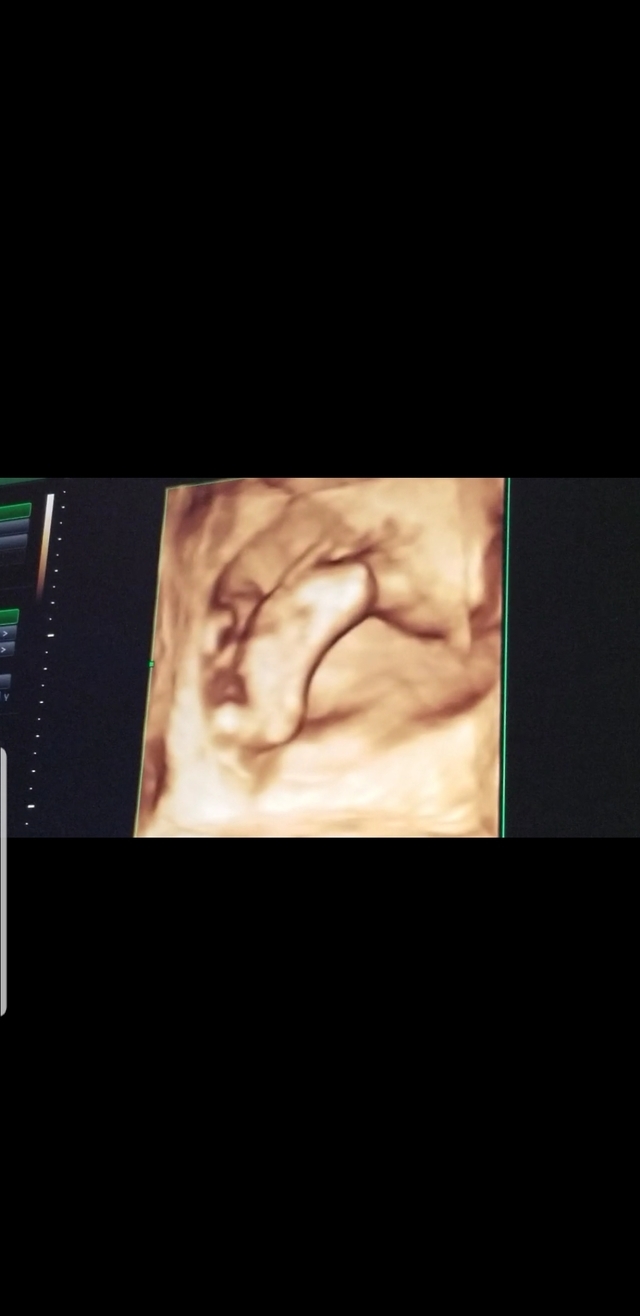

13週1日(13w1d・男の子)|ぽよぷに さん(27歳)

初めての4Dエコー。狭い子宮の中で、右手をあげているところがなんともたまらなくかわいい。生まれてからも右手をいつもあげているのかな?と想像がたくさん膨らみ、会える日が待ち遠しい気持ちでした。

つわりが辛い時だったけど、エコーを見て元気づけられたよ。この頃には、男の子確定のようなお言葉を頂きました!4Dエコーがこんなにハッキリ見えるとは思ってなく、ぜひおすすめします。